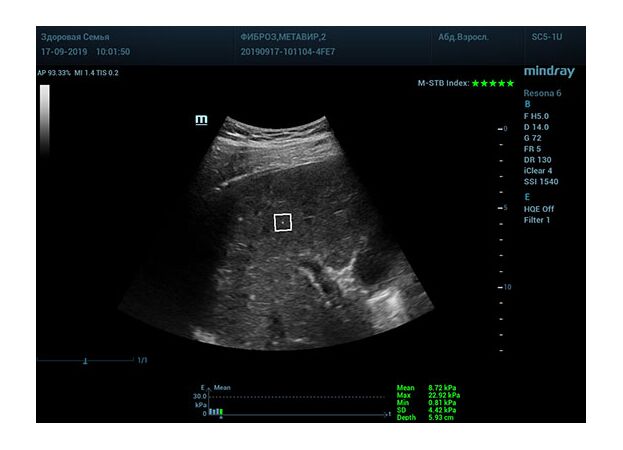

Определение плотности печени. Не ошибся ли оператор при измерении эластических свойств печени? Для оценки критериев качества предусмотрен индекс MBT, который покажет насколько «твердой» была рука оператора и двигалась ли печень. При MBT 5* рука тверда и показатели достоверны. Для оценки качества результатов используется IQR индекс, отображающий колебания показателей в точке измерения при расчете медианы. Показатели при IQR <30% считаются приемлемыми. Техника сканирования через межреберные промежутки требует размещение окна интереса на несколько сантиметром ниже капсулы, для исключения эффекта реверберации. Установка ROI на паренхиму без захвата сосудов, для исключения погрешностей измерения.

Стадия фиброза определяется по системе METAVIR Staging, построенной на данных биопсии и сопоставлении с данными эластографии. Своевременная диагностика фиброза, и начало его лечения, залог благоприятного исхода заболевания.